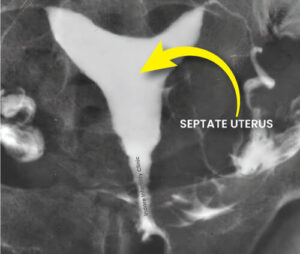

SeptateUterus